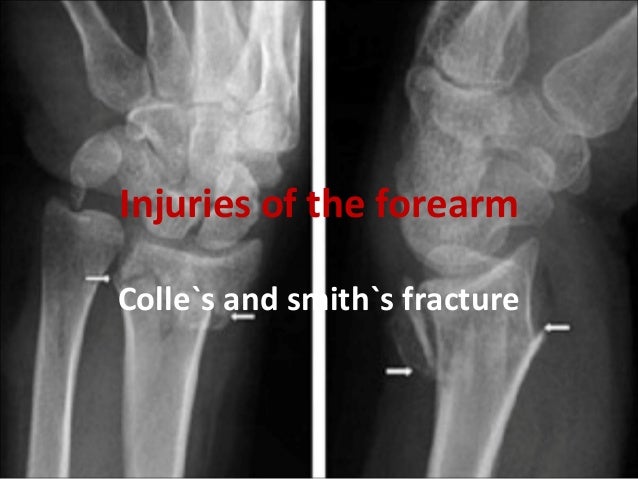

It is also known as a reverse colles fracture since the more common colles fracture features a dorsal displacement of the distal fracture fragment.

Smith vs colles fracture. A smith s fracture is a fracture of the distal radius. A smith fracture is an eponym for an extraarticular fracture of the distal radius featuring a volar displacement or angulation of the distal fragment. The colles fracture is one of the most common and challenging of the fractures.

It is caused by a direct blow to the dorsal forearm or falling onto flexed wrists as opposed to a colles fracture which occurs as a result of falling onto wrists in extension. Colles vs smith fracture an opposite to it depending on the severity of the injury one may experience pain while moving the wrist. Colles fractures are the most common type of distal radial fracture and are seen in all adult age groups and demographics.

Nabil ebraheim 183 583 views. Classically these fractures are extra articular transverse fractures and can be thought of as a reverse colles fracture. The distal fracture fragment is displaced volarly as opposed to a colles fracture which the fragment is displaced dorsally.

Depending on the severity of the impact there may be one or many fragments and it. Smith s fracture this describes the volar angulation of the distal fragment of an extra articular fracture of the distal radius the reverse of a colles fracture with or without volar displacement. The difference between colles fracture and smith s fracture is that the former is caused by a direct blow onto extended wrists while in the latter it occurs due to a direct blow on flexed wrists.